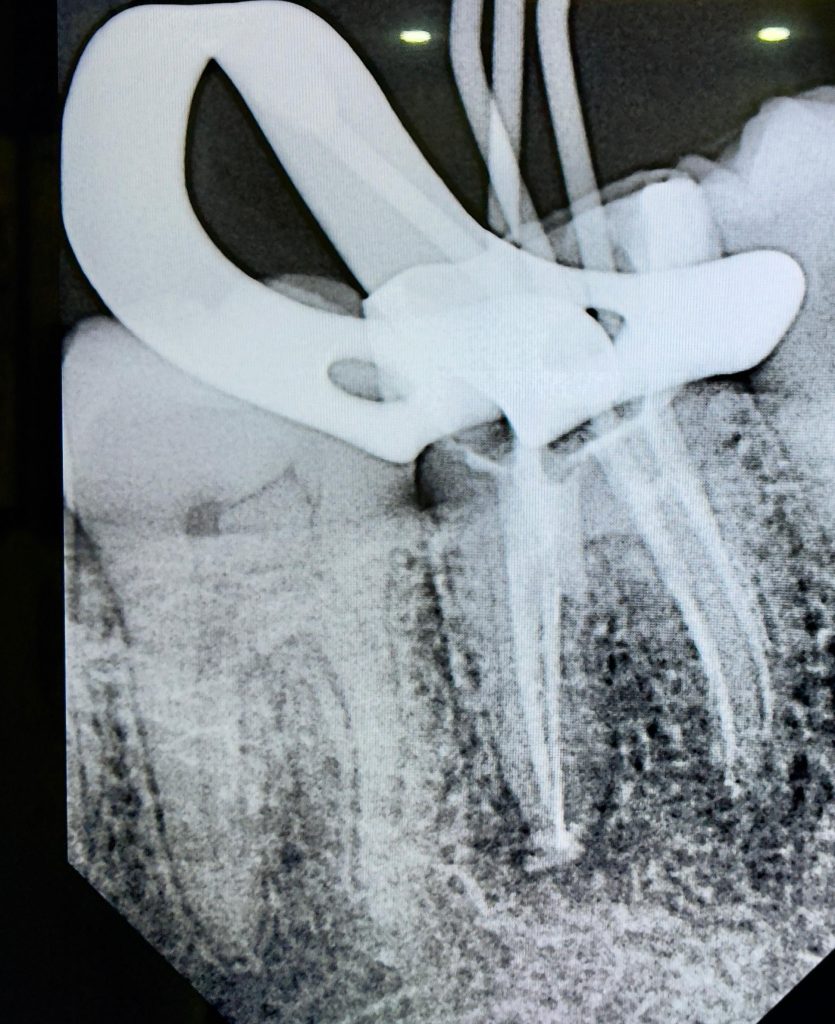

Clinical and Radiographic Findings

- Inadequate root canal obturation with voids.

- Missed canal anatomy suspected.

- Overhanging proximal restoration and subgingival distal margin.

- Associated periapical radiolucency.

- Compromised coronal seal.

Endodontic Retreatment

- Previous root filling material removed using rotary retreatment files and solvents.

- Working length established using electronic apex locator.

- Apical patency regained and canal shaping completed using reciprocating NiTi files.

- Canals obturated using warm vertical compaction and bioceramic sealer to optimise apical seal.

- Radiographic healing observed – periapical lesion resolved.

- Surrounding bone density improved.